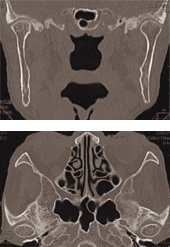

図❹ CT画像。顎骨の骨髄炎像や膿瘍形成、顎関節部の癒着、顎関節腔の拡大は認められなかった

CT画像:咀嚼筋の腫脹や膿瘍形成は認められなかった。また、顎関節部の著明な骨の変形や癒着、顎関節腔の拡大は認められなかった(図❹)。